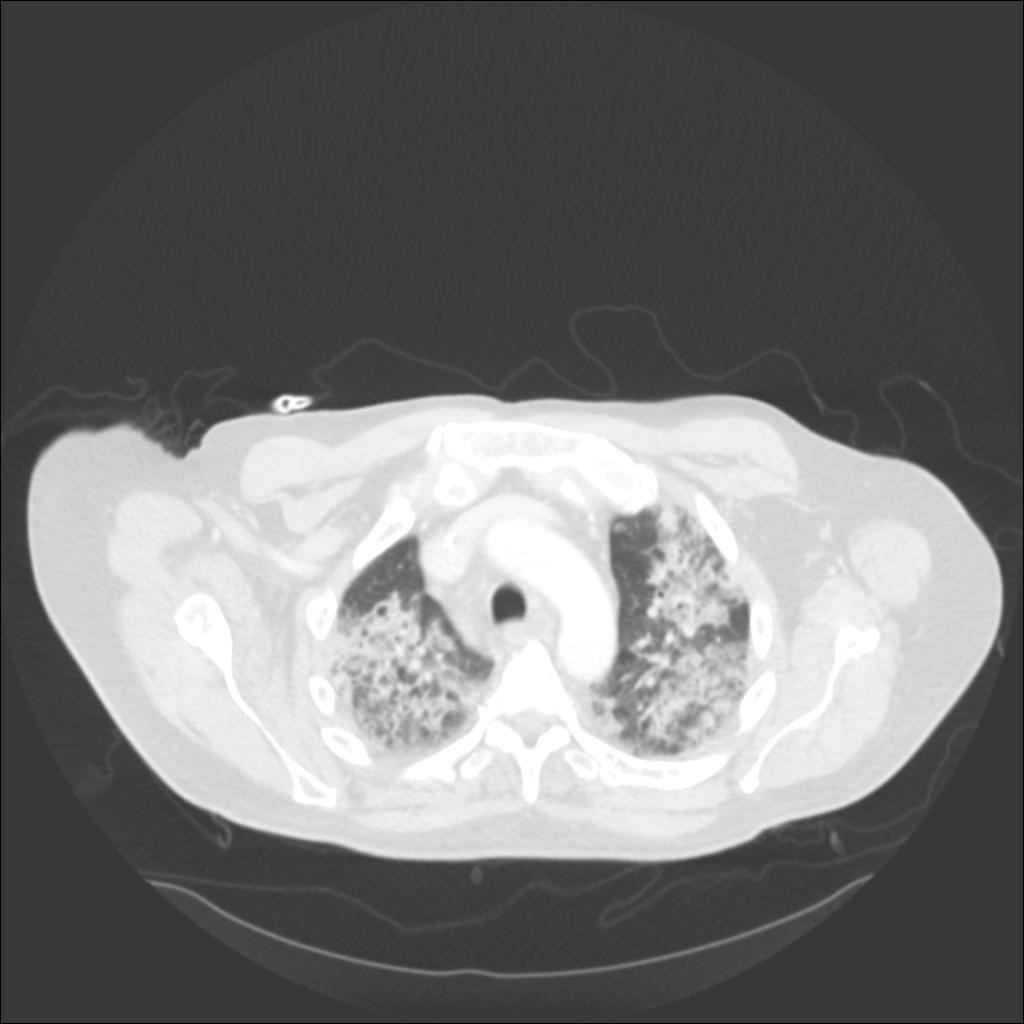

In our patient, the chest radiograph revealed multifocal alveolar infiltrates predominantly in the right upper lobe, left upper lobe, and left lower lobe. Chest CT revealed patchy ground glass and consolidative infiltrates throughout both lungs.